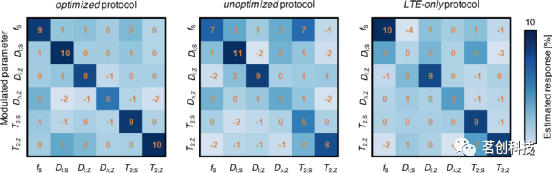

图4显示了各种协议对参数变化的敏感性。使用优化协议生成的数据进行训练的网络对所有参数都很敏感,但略微低估了变化的幅度,特别是在DΔ;Z中。特定参数调制对其余未调制参数的估计没有重大影响。但当T2;Z增加10%时的情况除外,这导致未变化的DI;S被高估了3%。与优化协议相比,未优化和LTE-only协议对小参数调制的敏感性较低,并且似乎对DΔ;Z(两种协议)和DI;S(LTE-only)的变化无响应。除了较低的灵敏度外,未优化协议还导致对未调制参数的估计不准确,10%的fS调制会导致T2;S错误增加7%。

图4.采集协议对10%参数调制的灵敏度。